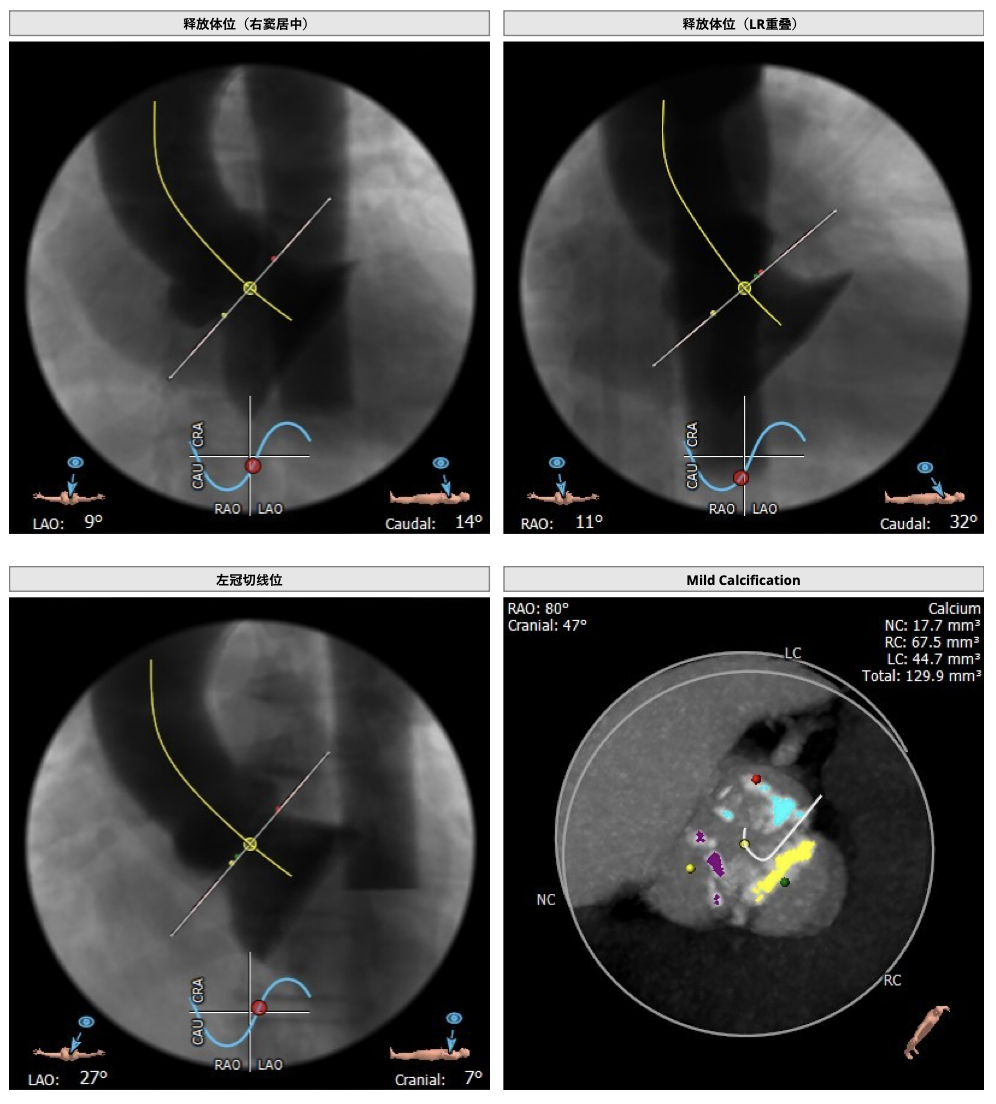

患者为三叶瓣,轻度钙化,右无、左右疑似部分融合,左冠高度可,右冠高度高,法式窦结构大,左室大,升主动脉未见明显扩张,右股动脉可作为主入路。

经分析研判,根据患者的瓣环径,结合患者瓣上结构,优先选用L26号的VenusA-Valve瓣膜,备L29,使用22mm球囊预扩,根据球扩情况进一步确认选瓣,瓣膜释放后结合造影和超声情况,决定是否后扩。